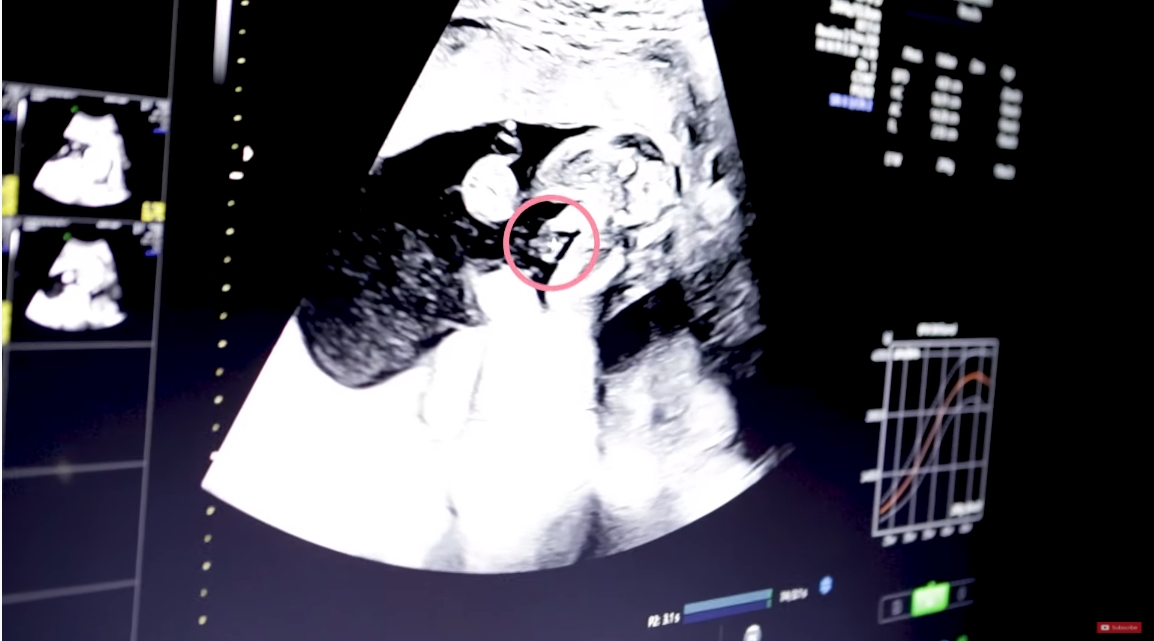

ในส่วนของการอัลตราซาวด์นั้น ก็รู้เลยว่าเบบี๋น้อยแข็งแรงสุด ๆ เพราะมีการเล่นขี่ม้ามาตั้งแต่ในท้องคุณแม่เลย บ่งบอกถึงความเป็นลูกชาย แถมยังจมูกโด่งหล่อเหลามาแต่ไกลเลยทีเดียว ซึ่งสรุปแล้วนั้น แม่ก้อยต้องเป็นคนจ่าย 1 ล้านบาท เพราะทายเพศลูกผิดนั่นเอง โดยจะเก็บเป็นเงินเข้าบัญชีให้ลูกไว้